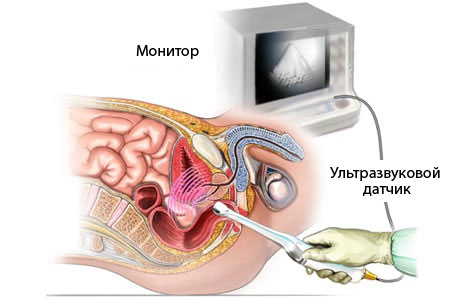

Діагностика цікавого положення жінки на ранніх термінах буде успішною лише за трансвагинальном дослідженні (коли датчик вводять у вагіну).

Найбільш точним методом ультразвукової діагностики є трансвагінальне дослідження. В ході цієї діагностичної процедури на спеціальний датчик одягають презерватив, після чого вводять у вагіну. Для отримання більш точного результату слід повністю спустошити сечовий міхур.

Трасвагінальний метод застосовують тільки для діагностики невеликих термінів вагітності. Надалі вагітних жінок обстежують трансабдомінальним методом, який вважається менш точним.